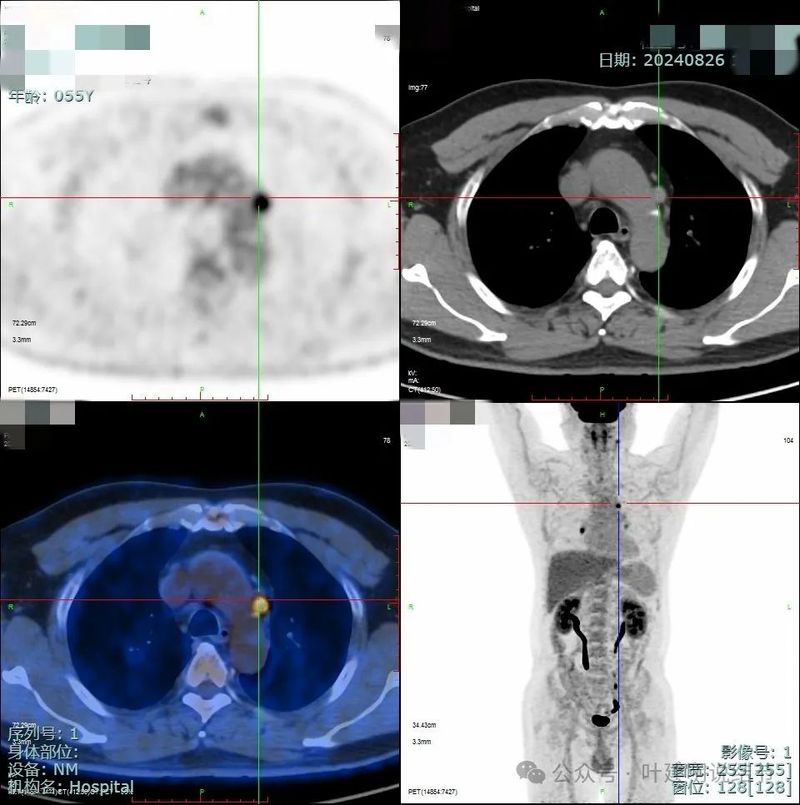

PET-CT检查情况:

PET检查结果示右肺上叶后段小结节,葡萄糖代谢轻度增高,考虑低代谢肿瘤性病变可能性大。